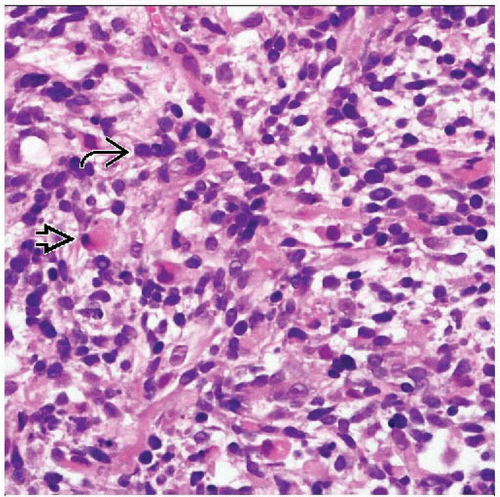

Embryonal Rhabdomyosarcoma Showing; (a) Several Rhabdomyoblasts Having

www.researchgate.net

www.researchgate.net

Webpathology.com: A Collection Of Surgical Pathology Images

www.webpathology.com

www.webpathology.com

orbit rhabdomyosarcoma embryonal webpathology rms comments

Microscopic Examination Of The Resected Embryonal Rhabdomyosarcoma

www.researchgate.net

www.researchgate.net

Embryonal Rhabdomyosarcoma Of The Orbit. A Diffuse Infiltrate Of

www.researchgate.net

www.researchgate.net